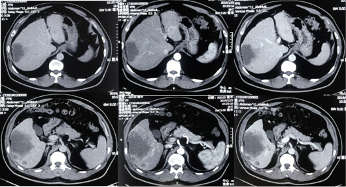

影像学检查:2019-01-23如图示。

患者肿瘤情况处于进展期HCC(IIIa),PVTT-II。肿瘤负荷重,左右叶均有病灶,肝右叶主病灶超过5 cm,周围多发播散子灶。门静脉一级分支(右支癌栓),与右叶主病灶相关。肝功能好,体能好。遂予局部+系统治疗。

该病例为男性,50岁乙肝多年,CT显示右叶主灶 > 5 cm,左右叶子灶,右支癌栓。但是有一个疑点左叶子灶与右叶病灶强化有所不同,查AFP:169.7 ng/mL,PIVKA II 433 mAu/mL,显示其AFP不够高,所以采用PIVKA II与之互补,体现了主治医生检查的细致、周全。此外,做肝穿活检HCC以弥补肿瘤标志物的不足,更体现该医生诊断的严谨性和规范性。诊断:CNLC;IIIa,肝功能 A5,ECOG评分 0。